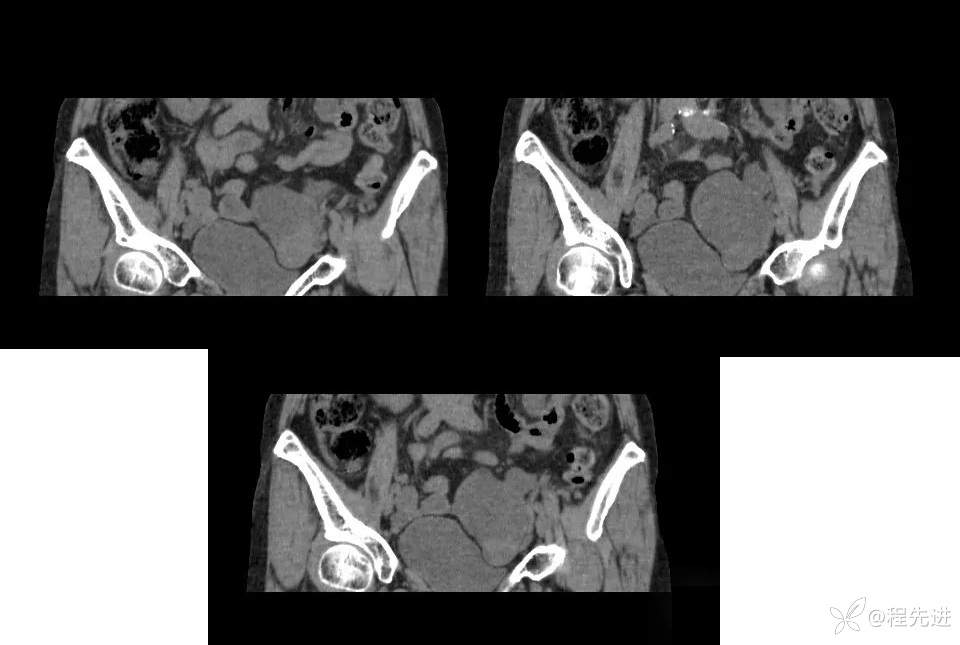

【患者信息】:女,59岁

【主诉】:下腹部不适2月,B超发现盆腔囊性包块。

实验室检查:CA125:239.1u/ml,CA72-4:99.64u/ml